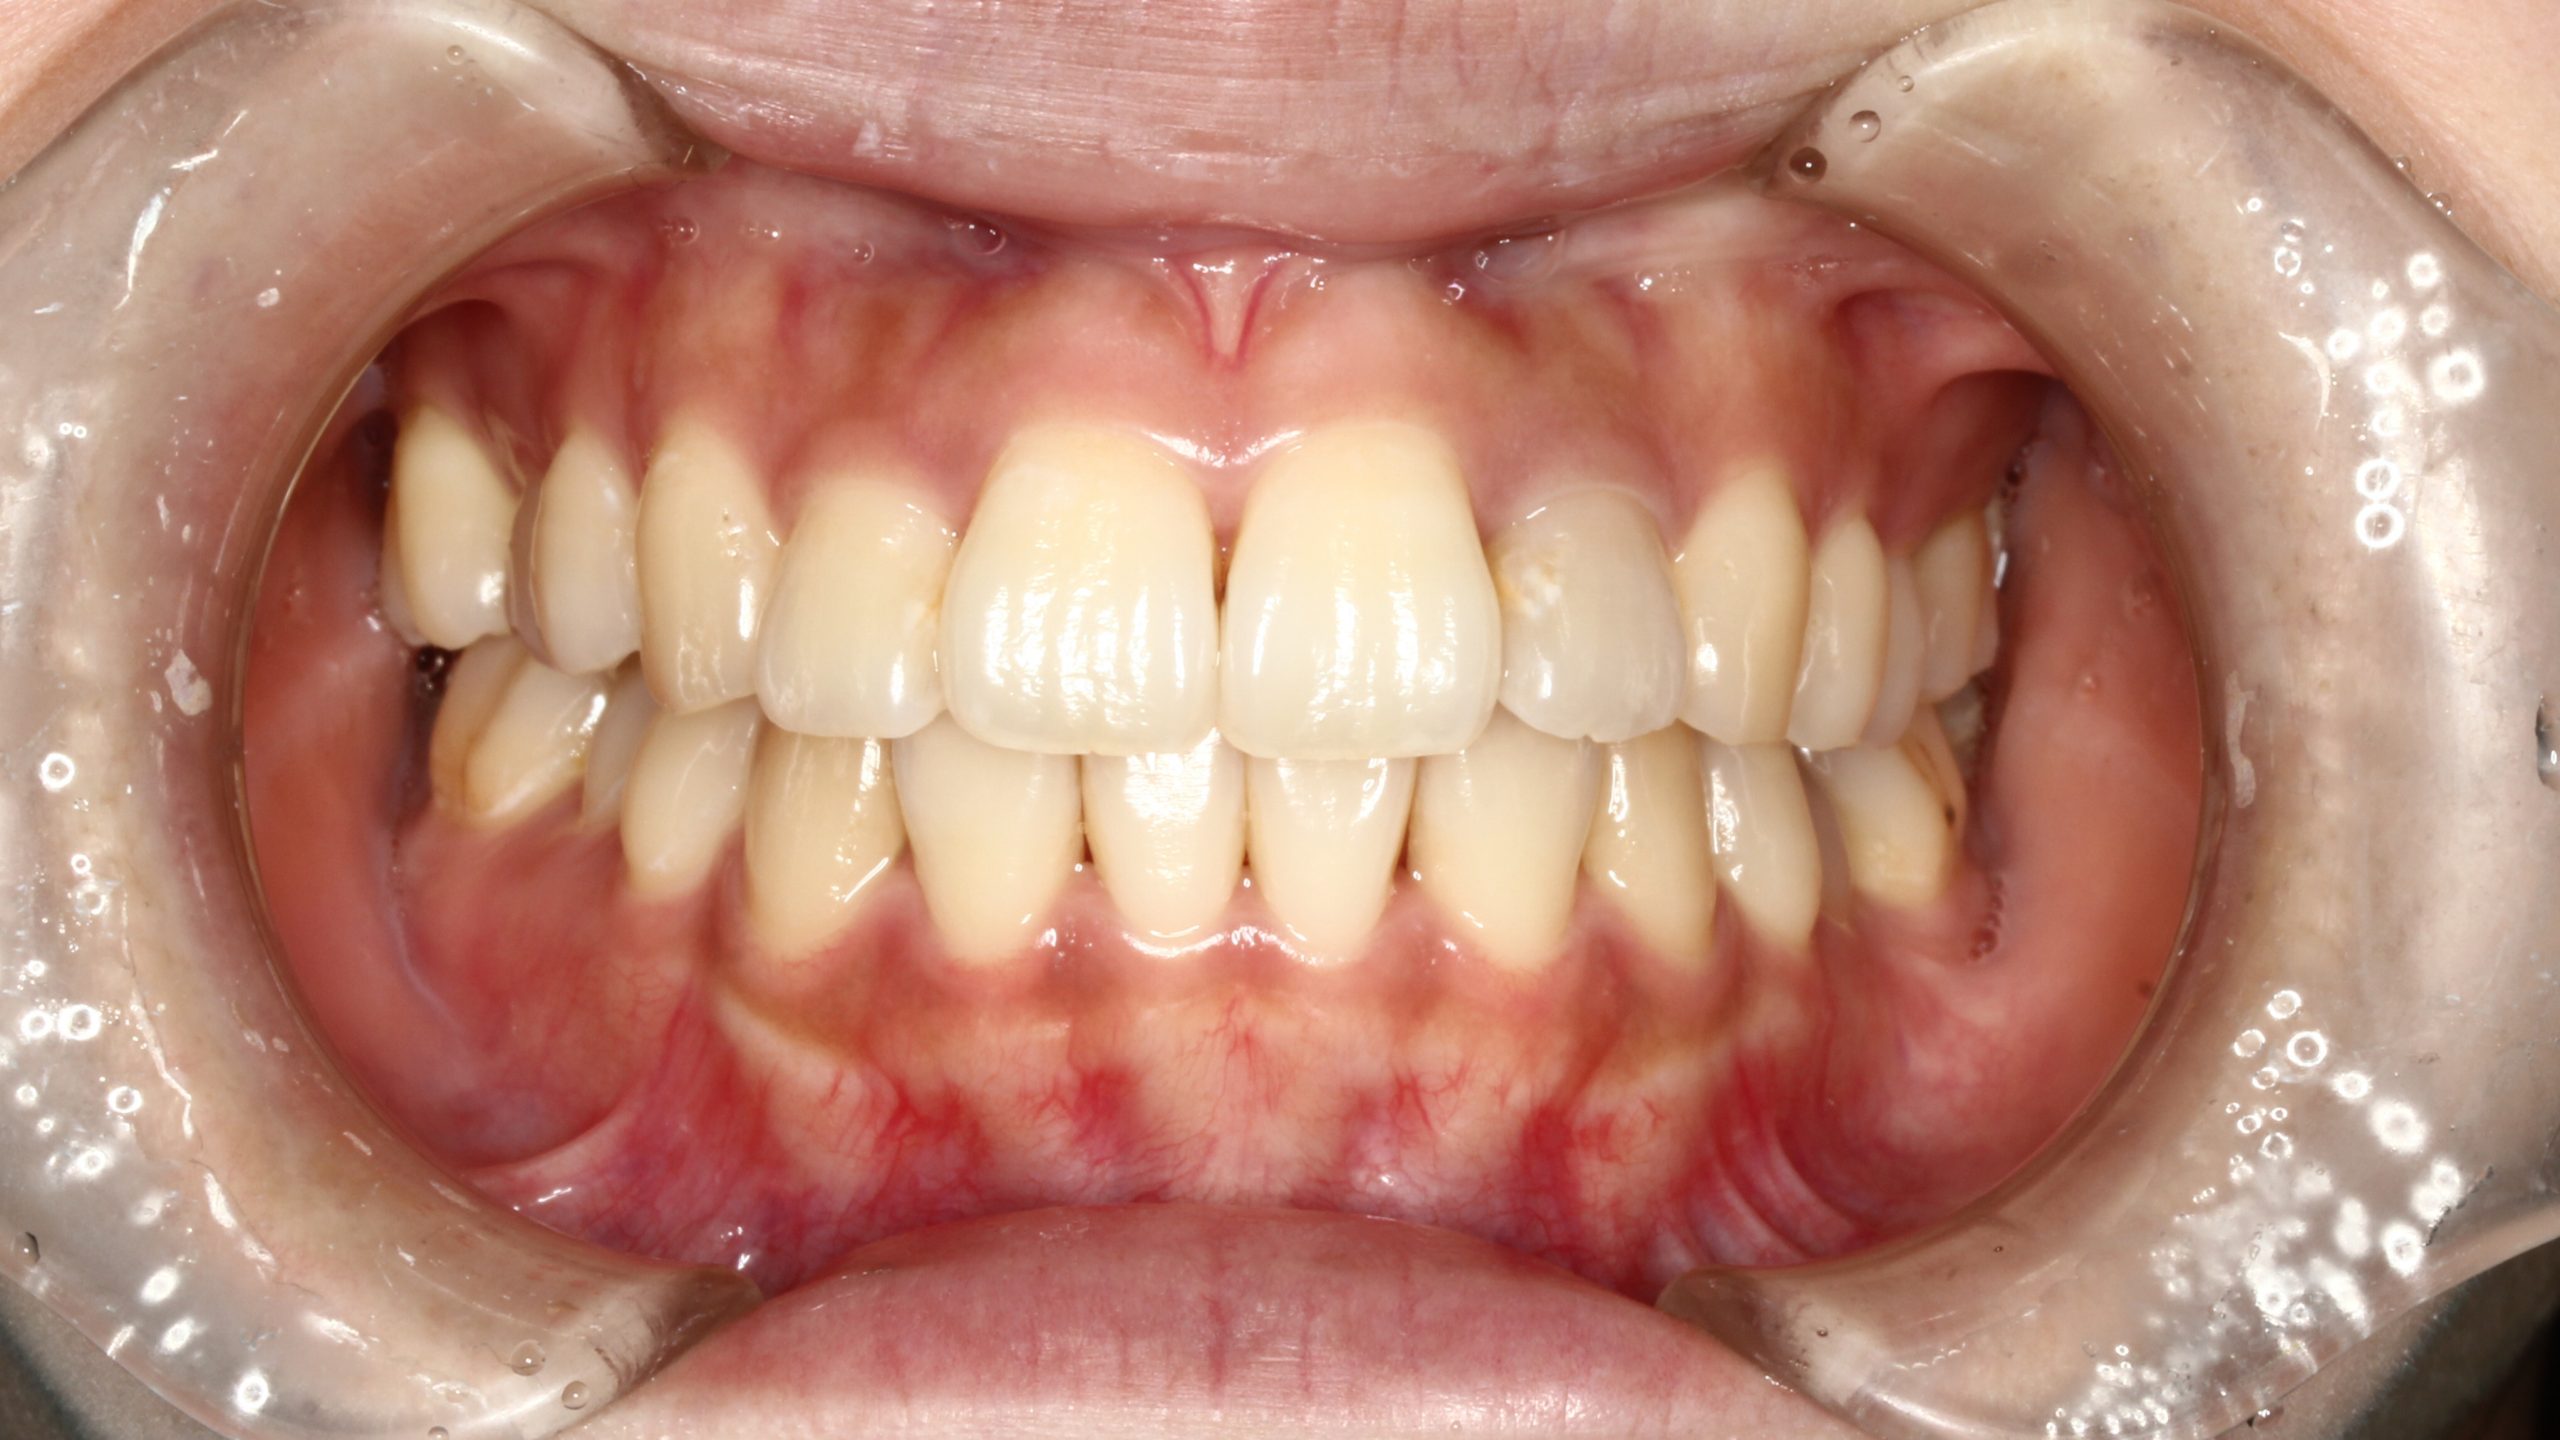

上の歯が出ている、嚙み合わせが悪い(治療期間:2年4か月/通院32回)

Before